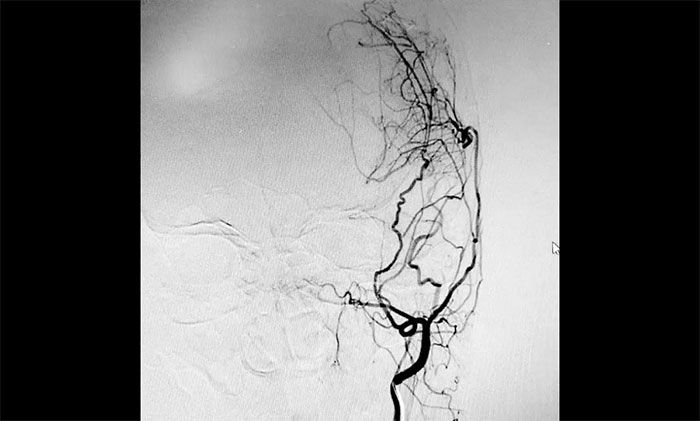

▲ DSA顯示左側(cè)腦供血側(cè)支循環(huán)已逐步建立

7月中旬,范先生遵照醫(yī)囑來醫(yī)院復(fù)查,不僅體重回到了腦出血前的水平,精神狀態(tài)也明顯好轉(zhuǎn)。再次行DSA檢查顯示,左側(cè)大腦中動脈遠(yuǎn)端血管豐富,表明該側(cè)腦供血側(cè)支循環(huán)已逐步建立,缺血腦組織得到了及時(shí)挽救,符合手術(shù)預(yù)期。